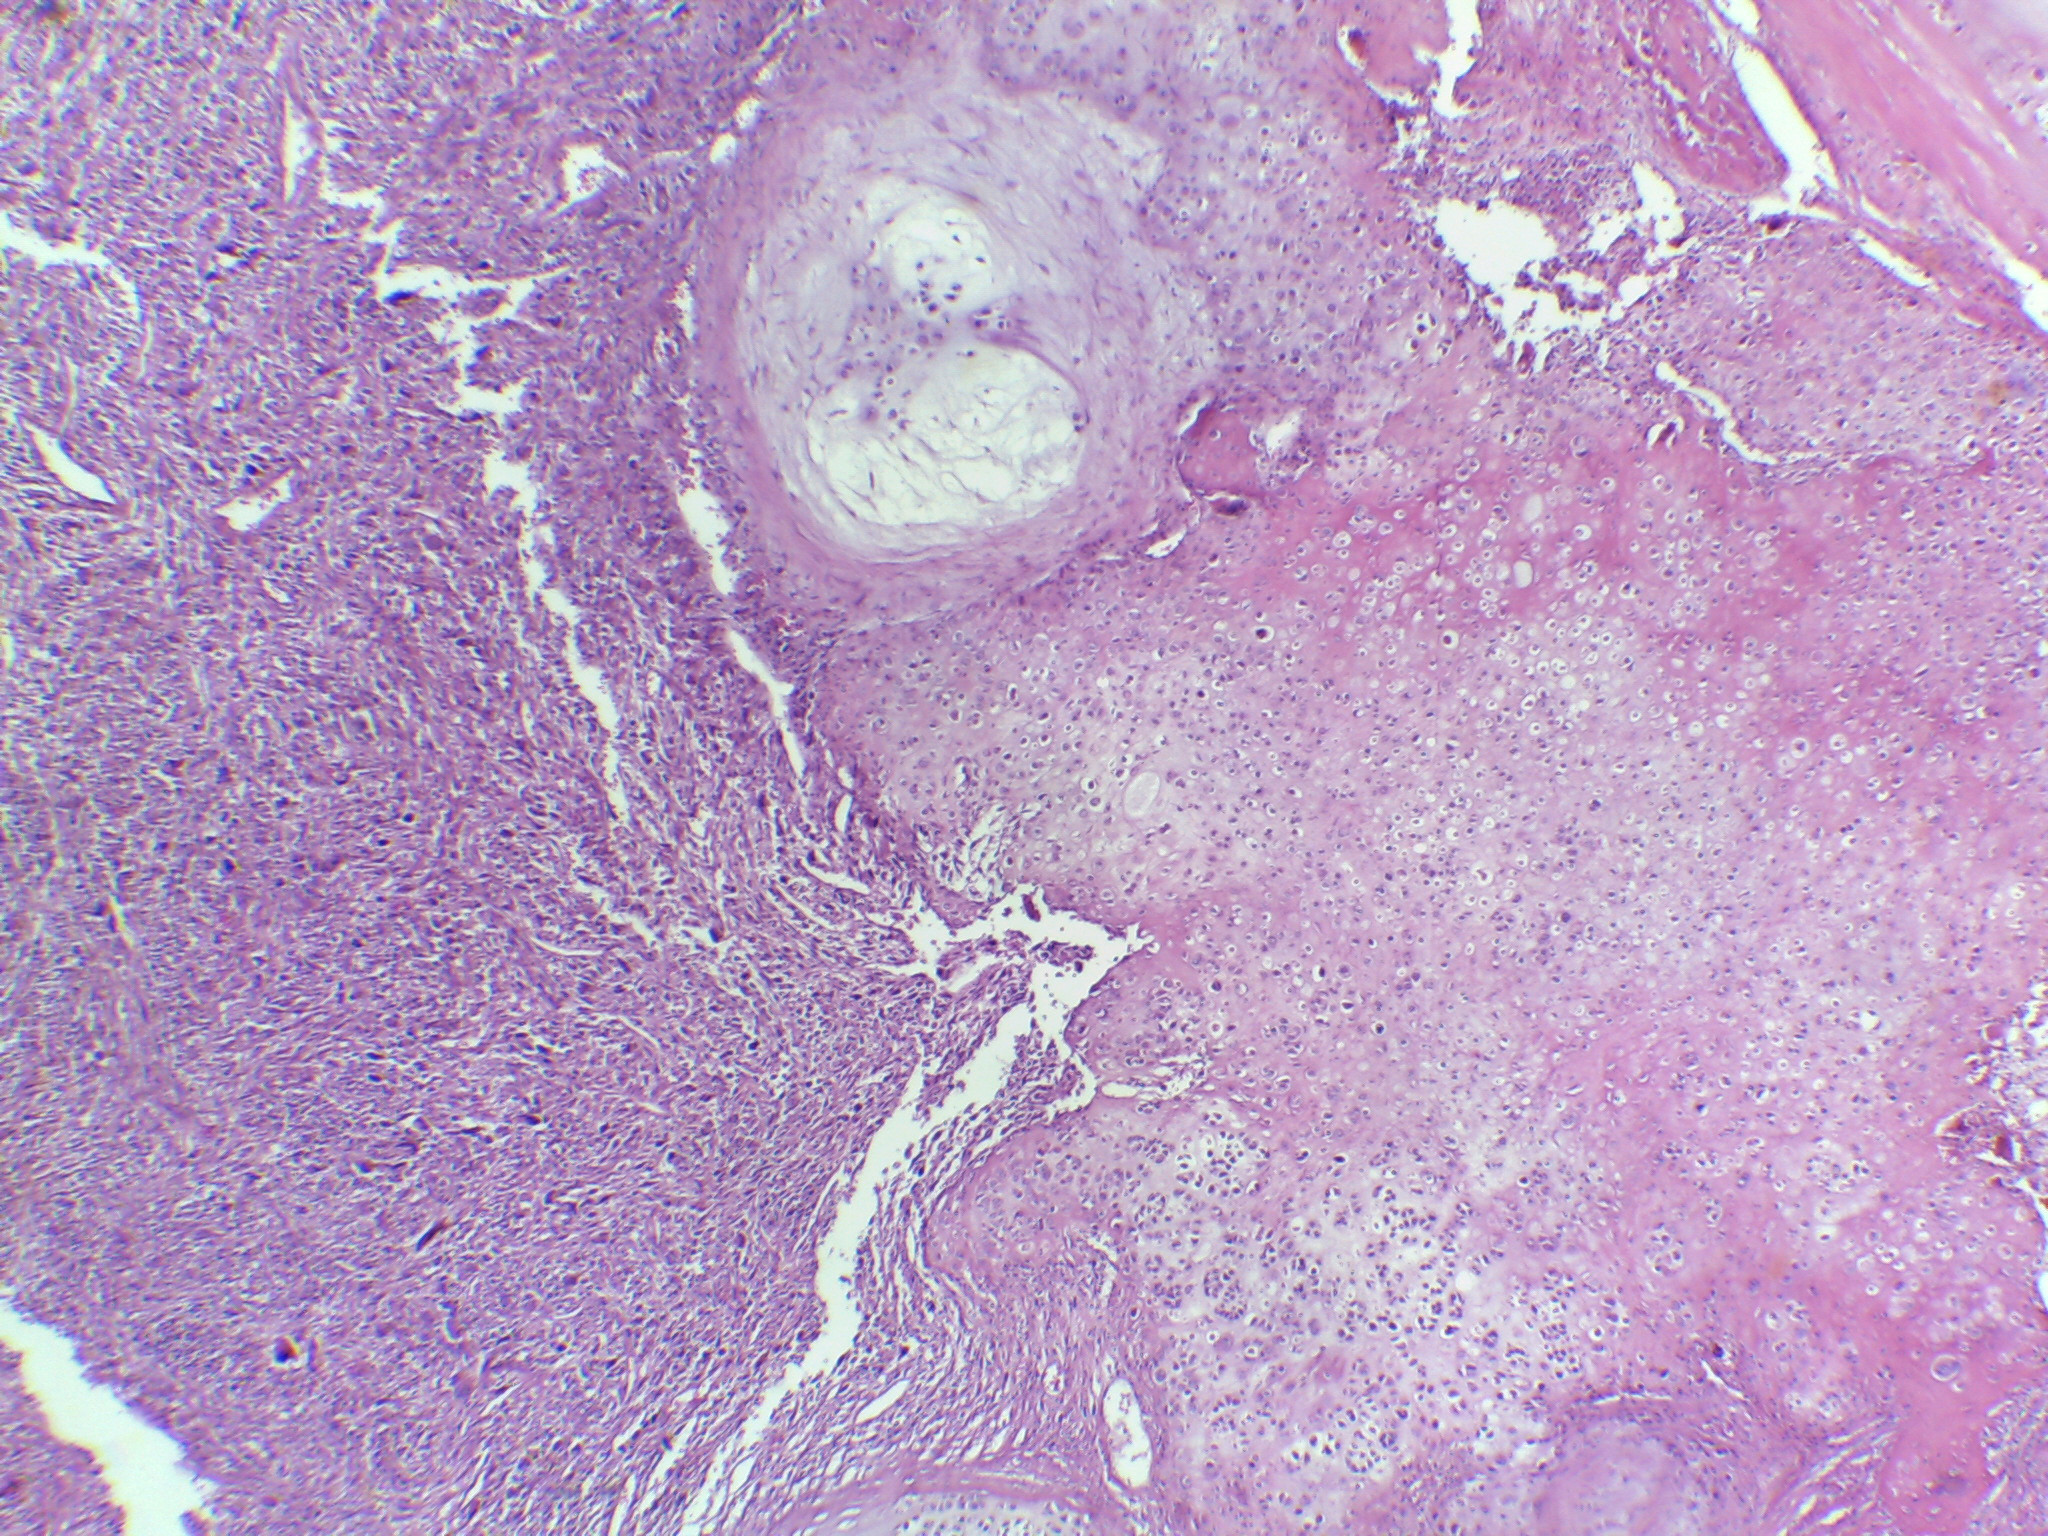

Mujer de 49 años. Dolor en pierna  de 2 años de evolución.

Dolor en pierna  de 2 años de evolución

Incremento de dolor

Fractura de fémur

Condrosarcoma desdiferenciado